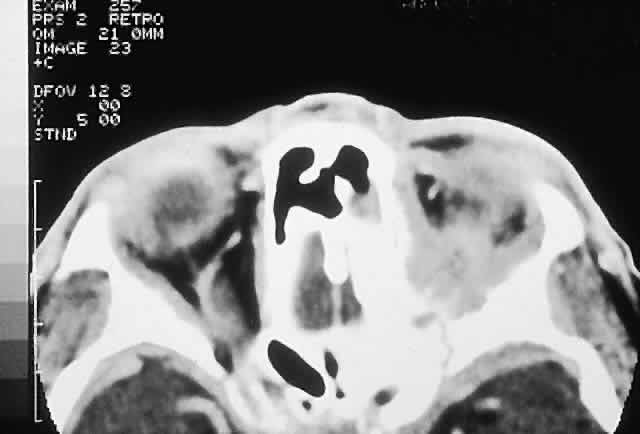

IMAGING. Ossifying fibroma starts as a monostotic lesion that expands the bone of origin in a well-circumscribed manner. However, with growth it may spread to involve adjacent bones and may even extend across the midline to involve both orbits. The characteristic CT appearance is of a round or ovoid mass with a well-defined, thin sclerotic margin (Fig. 3). Centrally, there is often a patchy pattern of osteoblastic and osteolytic areas.46

Fig. 3. A. A 24-year-old man with a 10-year history of increasing right proptosis and a history of ossifying fibroma excised from the right ethmoid and sphenoid 12 years previously. Examination revealed 3 mm of proptosis and 2 mm of lateral globe displacement. B. CT showed a heterogeneous mass with a sclerotic margin involving the right ethmoid and orbit. C and D. After excision, the histology revealed a fibrous stroma containing small spherical ossicles characteristic of the psammomatoid variant of ossifying fibroma (hematoxylin-eosin; C × 20, D × 50). There has been no recurrence in 18 years of follow-up.

HISTOPATHOLOGY. Macroscopically, the lesional tissue is white to red and has a largely soft fibrous texture with variable grittiness, dependent on the amount of osteoid. Microscopically, it consists of a cellular vascular stroma containing trabeculae of lamellar bone. These bony trabeculae often have a thin surrounding of osteoid and, in contrast to fibrous dysplasia, display prominent osteoblastic rimming. There may also be osteoblasts as well as a few foci of giant cells in the stroma. If larger specimens are available, they may demonstrate a zonation phenomenon, seen as an increasing maturity of bone toward the periphery.19

In the psammomatoid variant described by Margo and colleagues,49 at least half of the tumor contains sphericular ossicles. This histologic pattern has been correlated with a more aggressive local behavior and a tendency to recur after incomplete excision.